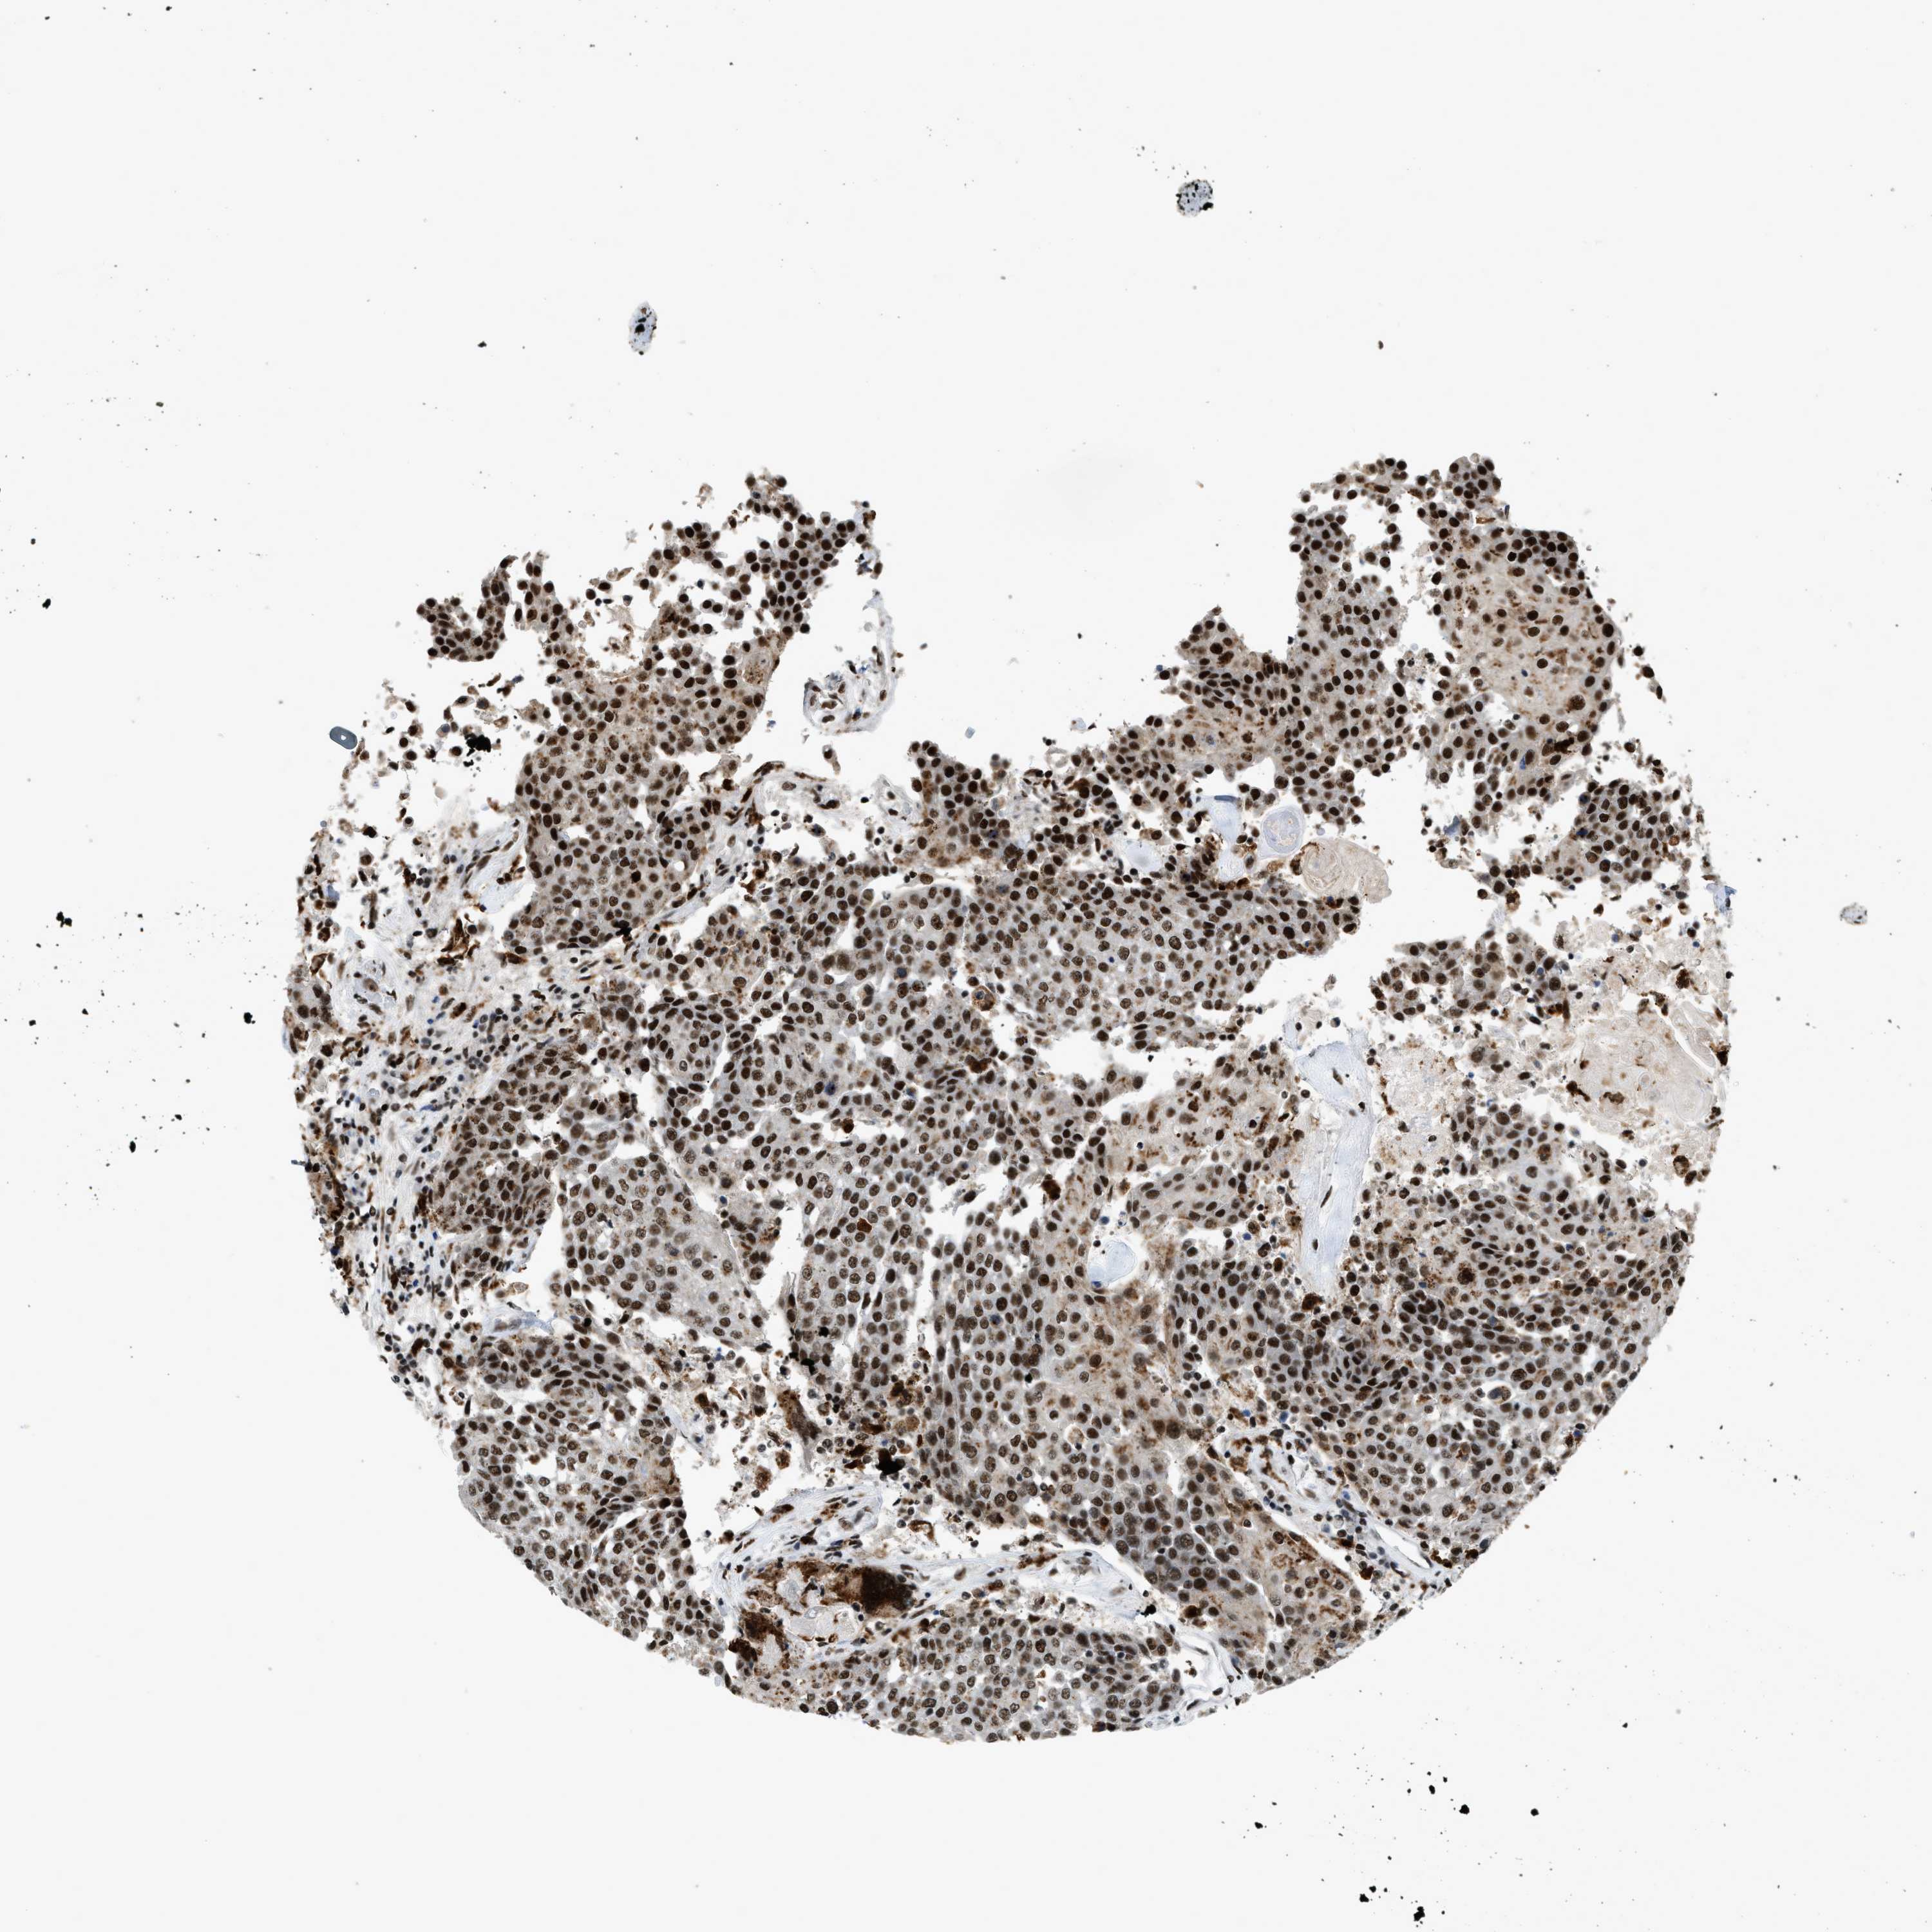

UROTHELIAL CANCER - Protein expressioni

A mouse-over function shows sample information and annotation data. Click on an image to view it in a full screen mode. Samples can be filtered based on level of antibody staining by selecting one or several of the following categories: high, medium, low and not detected. The assay and annotation is described here.

Note that samples used for immunohistochemistry by the Human Protein Atlas do not correspond to samples in the TCGA dataset.

Antibody stainingi

Antibody staining in the annotated cell types in the current human tissue is reported as not detected, low, medium, or high, based on conventional immunohistochemistry profiling in selected tissues. This score is based on the combination of the staining intensity and fraction of stained cells.

Each image is clickable and will lead to virtual microscopy that enables deeper exploration of all samples and also displays staining intensity scores, fraction scores and subcellular localization as well as patient and tissue information for each sample.

Antibody HPA019841

Antibody HPA019859

Antibody HPA029912

Staining

High

Medium

Low

Not detected

Intensity

Strong

Moderate

Weak

Negative

Quantity

>75%

75%-25%

<25%

None

Location

Urothelial carcinoma, Low grade

Urothelial carcinoma, High grade